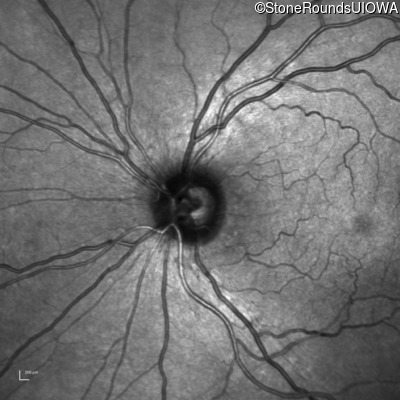

Infrared Fundus Photograph - Left - Count Fingers 4' sc

Exemplar